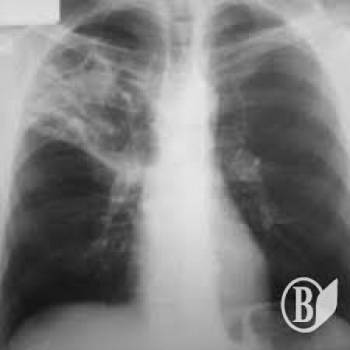

ЧИТАЙТЕ ТАКЖЕ: Уязвимые категории населения проверили на туберкулез